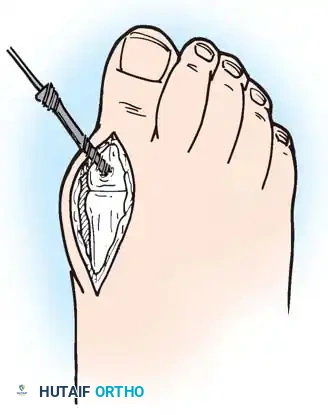

1. Approach: A dorsal longitudinal incision is made medial to the EHL tendon, extending from the mid-shaft of the first metatarsal to the interphalangeal joint.

2. Joint Preparation: The capsule is incised, and the collateral ligaments are released. The severely eroded articular surfaces of the first metatarsal head and the base of the proximal phalanx are resected. Cup-and-cone reamers are highly recommended to preserve length while allowing multi-planar adjustment.

3. Positioning: The hallux is positioned in 10 to 15 degrees of valgus and 15 to 20 degrees of dorsiflexion relative to the first metatarsal shaft. Neutral rotation must be confirmed to ensure the toenail faces directly dorsal.

4. Fixation: Rigid internal fixation is achieved using a dorsal contoured titanium plate and a lag screw across the arthrodesis site.

Fig. 81-2 (A, B) Preoperative clinical views showing severe dorsal subluxation-dislocation of lesser toes. (C) Plantar view post-resection of metatarsal heads. (D) Excellent postoperative clinical alignment following first MTP arthrodesis and lesser metatarsal head excision.